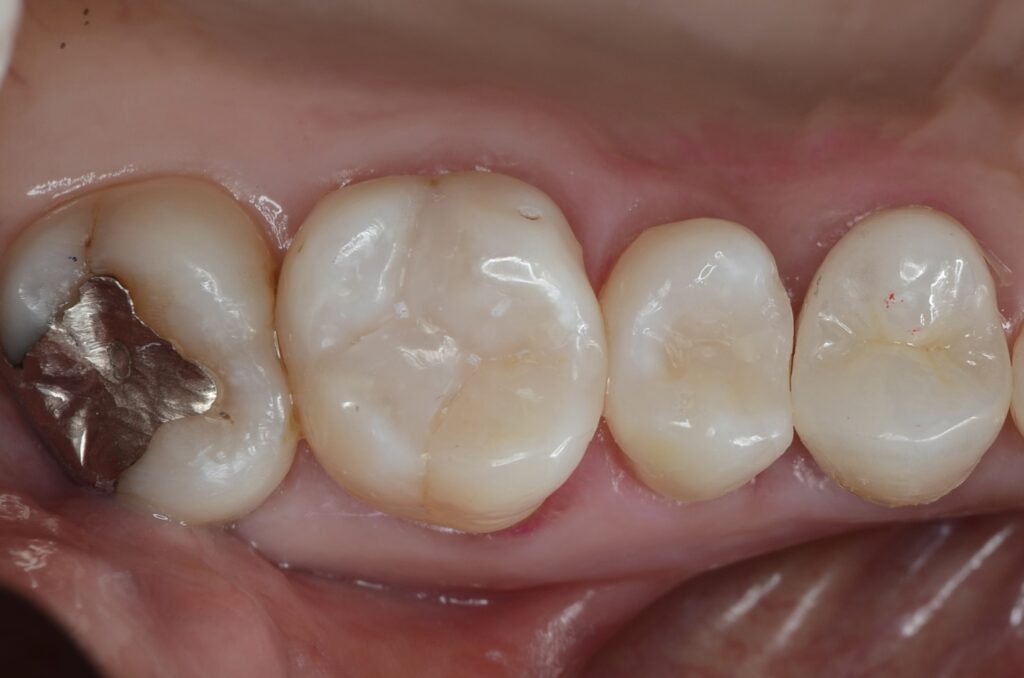

60代 虫歯治療 ダイレクトボンディング #34

Before

After

| 年齢 | 60代 | 治療方法 | ダイレクトボンディング |

|---|---|---|---|

| 性別 | 男性 | 通院回数 | 4回 |

| 主訴 | むし歯を治したい 。歯を長持ちさせたい | 費用 | 346,500円(税込) |

| 治療のメリット | 歯を削る量を少なくできる・自然な見た目・境目がピッタリできる | ||

| 治療のデメリット | 大きい虫歯治療には適応できない場合がある | ||